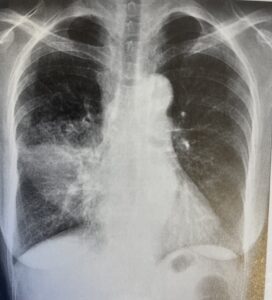

咳が続いているなど、肺炎が疑われる患者さんには、胸部レントゲン写真も実施します。

【肺炎の胸部レントゲン写真】